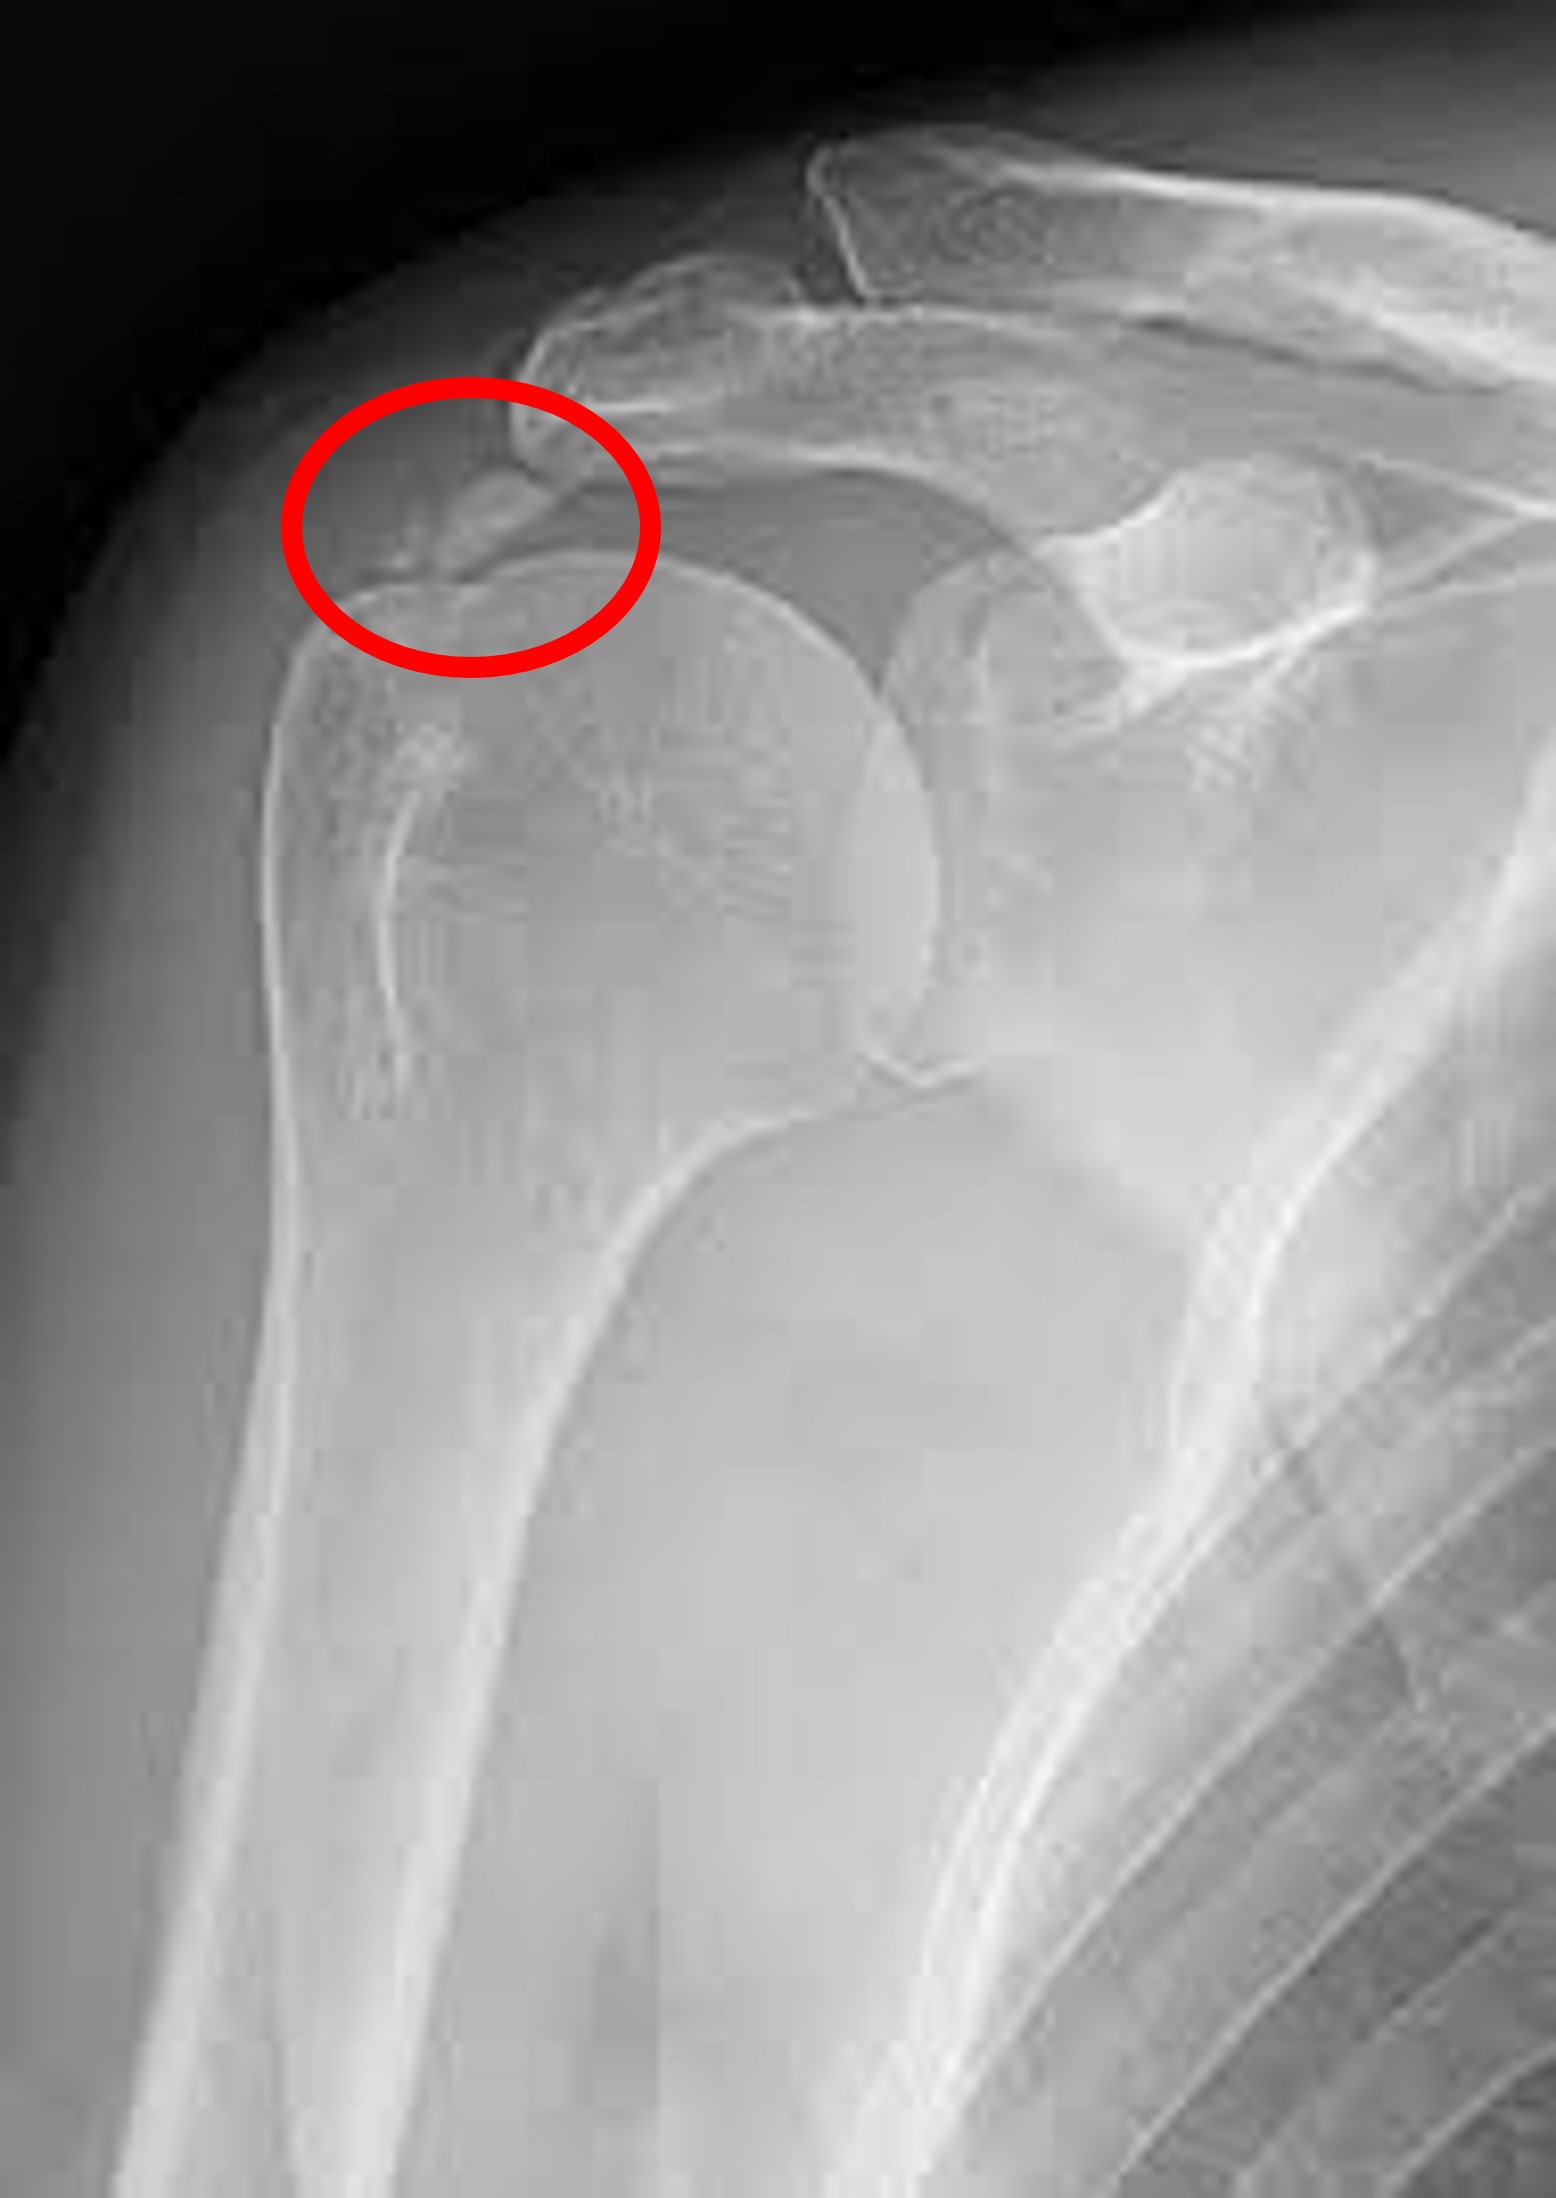

2. 초음파 :

초음파는 X-ray에서 관찰할 수 없는 연부조직들인 인대, 근육, 관절 내 염증 물질 등을 관찰할 수 있는 검사입니다. MRI에 비해서 저렴한 비용으로 검사할 수 있으며, 정적인 자세로 오랫동안 누워있어야 이미지를 얻을 수 있는 MRI와 다르게, 환자의 신체를 이리저리 움직이면서 다이나믹하게 여러부위를 실시간으로 관찰할 수 있는 장점이 있습니다. 다만 초음파 기기의 특성상 술자의 숙련도에 따라 얻을 수 있는 이미지의 편차 및 진단률의 차이가 있을 수 있습니다.

초음파는 파열된 회전근개 건조직을 직접적으로 이미지화 시킬 수 있으며, 염증이 심한 경우 동시에 주사치료를 시행할 수 있는 장점이 있어, 널리 사용되는 검사입니다.